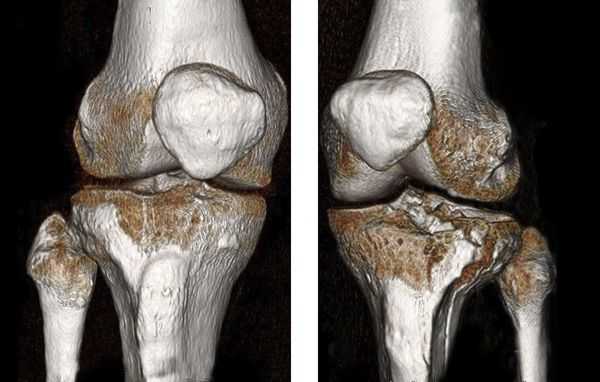

Мыщелковые переломы бедра являются внутрисуставными. Чаще встречаются у пожилых, возникают при падении или ударе по колену. Сопровождаются резкой болью в области колена и нижней части бедра. Опора и движения ограничены. Коленный сустав отечен, определяется гемартроз. При переломах мыщелков со смещением наблюдается отклонение голени внутрь либо кнаружи. Для уточнения диагноза назначают рентгенографию коленного сустава. При поступлении сустав пунктируют, затем накладывают гипс или скелетное вытяжение. Если отломки невозможно сопоставить, проводят операцию - остеосинтез винтами, пластиной или болтами-стяжками.

Переломы мыщелков большеберцовой кости являются внутрисуставными и чаще возникают вследствие падения с высоты. Возможны как изолированные переломы внутреннего или наружного мыщелка, так и одновременный перелом двух мыщелков. Коленный сустав отечен, в нем определяется гемартроз. Движения и опора болезненны, резко затруднены. Диагноз уточняют на основании рентгенографии, реже используют МРТ коленного сустава. Лечение - пункция, блокада места перелома, при переломах ноги без смещения осуществляют иммобилизацию гипсовой повязкой, при повреждениях со смещением накладывают скелетное вытяжение либо выполняют операцию (остеосинтез пластинами, винтами или аппаратом Илизарова).

В некоторых случаях, если требуется детальная диагностика нескольких сегментов голени или пациент находится в тяжёлом состоянии, показана компьютерная томография с 3d-реконструкцией кости. Исследование можно проводить и при вынужденном положении конечности, но такой томограф есть не во всех клиниках. Поэтому в некоторых случаях, если информации недостаточно, делаются уточняющие прицельные рентгеновские снимки отдельных сегментов кости.

![Компьютерная томография голени]()